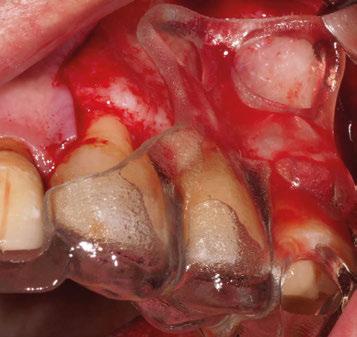

Para ilustrar el proceso, presentamos el caso de una mujer joven diagnosticada de carcinoma adenoide quístico en la región posterior del hemipaladar izquierdo (Figuras 1 y 2). El procedimiento quirúrgico realizado fue una

maxilectomía parcial que incluyó las piezas 24-26 y desde el reborde alveolar hasta la base del cráneo (Figuras 3 y 4). En este caso, la órbita y el globo ocular pudieron ser preservados. La reconstrucción inmediata se realizó mediante un colgajo de músculo temporal homolateral (Figura 5) y el defecto de la fosa temporal fue cubierto mediante una malla de titanio. Posteriormente, la paciente recibió radioterapia (Figuras 6 y 7). 2 años más tarde se diseñó un IS con anclaje en el arbotante nasomaxilar, zona subnasal izquierda

Figura 3. Maxilectomía parcial.

Figura 4. Defecto maxilar tras resección del tumor.

y lo que se pudo preservar del hueso malar. Se añadió una malla sinterizada infraorbitaria para dar volumen a la mejilla y se planificaron dos brazos de conexión que emergieran en las posiciones 24 y 26 de forma subgingival (Figuras 8 y 9). La superficie interna que apoyaba en el hueso era de titanio microrrugoso, y la superficie externa y conectores de titanio pulido y hexágono externo universal (Figuras 10 y 11). La cirugía se hizo bajo anestesia general en infiltración con anestesia local (4% articaína, 1:100.00 epinefrina), levantando el

colgajo cutáneo de la mejilla por vía intraoral, preservando el colgajo temporal para no comunicar con el remanente de la cavidad naso maxilar (Figura 12). Se emplearon 10 tornillos de osteosíntesis de 1,9 mm y la estabilidad primaria obtenida fue excelente (Figura 13)